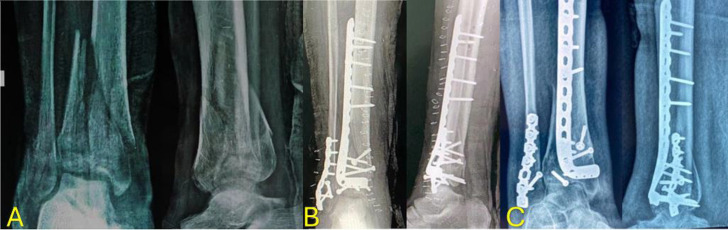

Methods: In a prospective trial, 30 patients were divided into two cohorts: a two-stage cohort with external fixation and secondary ORIF (15 patients) and a one-stage primary ORIF cohort (15 patients). We compared the two cohorts' rates of infection (deep or superficial infection), non-union, malunion, length of hospital stay, patient satisfaction with the American Orthopaedic Foot and Ankle Society (AOFAS) score, and pain level.

Results: All assessed variables showed no significant variations between the two cohorts, except for hospital stay duration, which was substantially more prolonged in the two-stage cohort.

Abstract Image